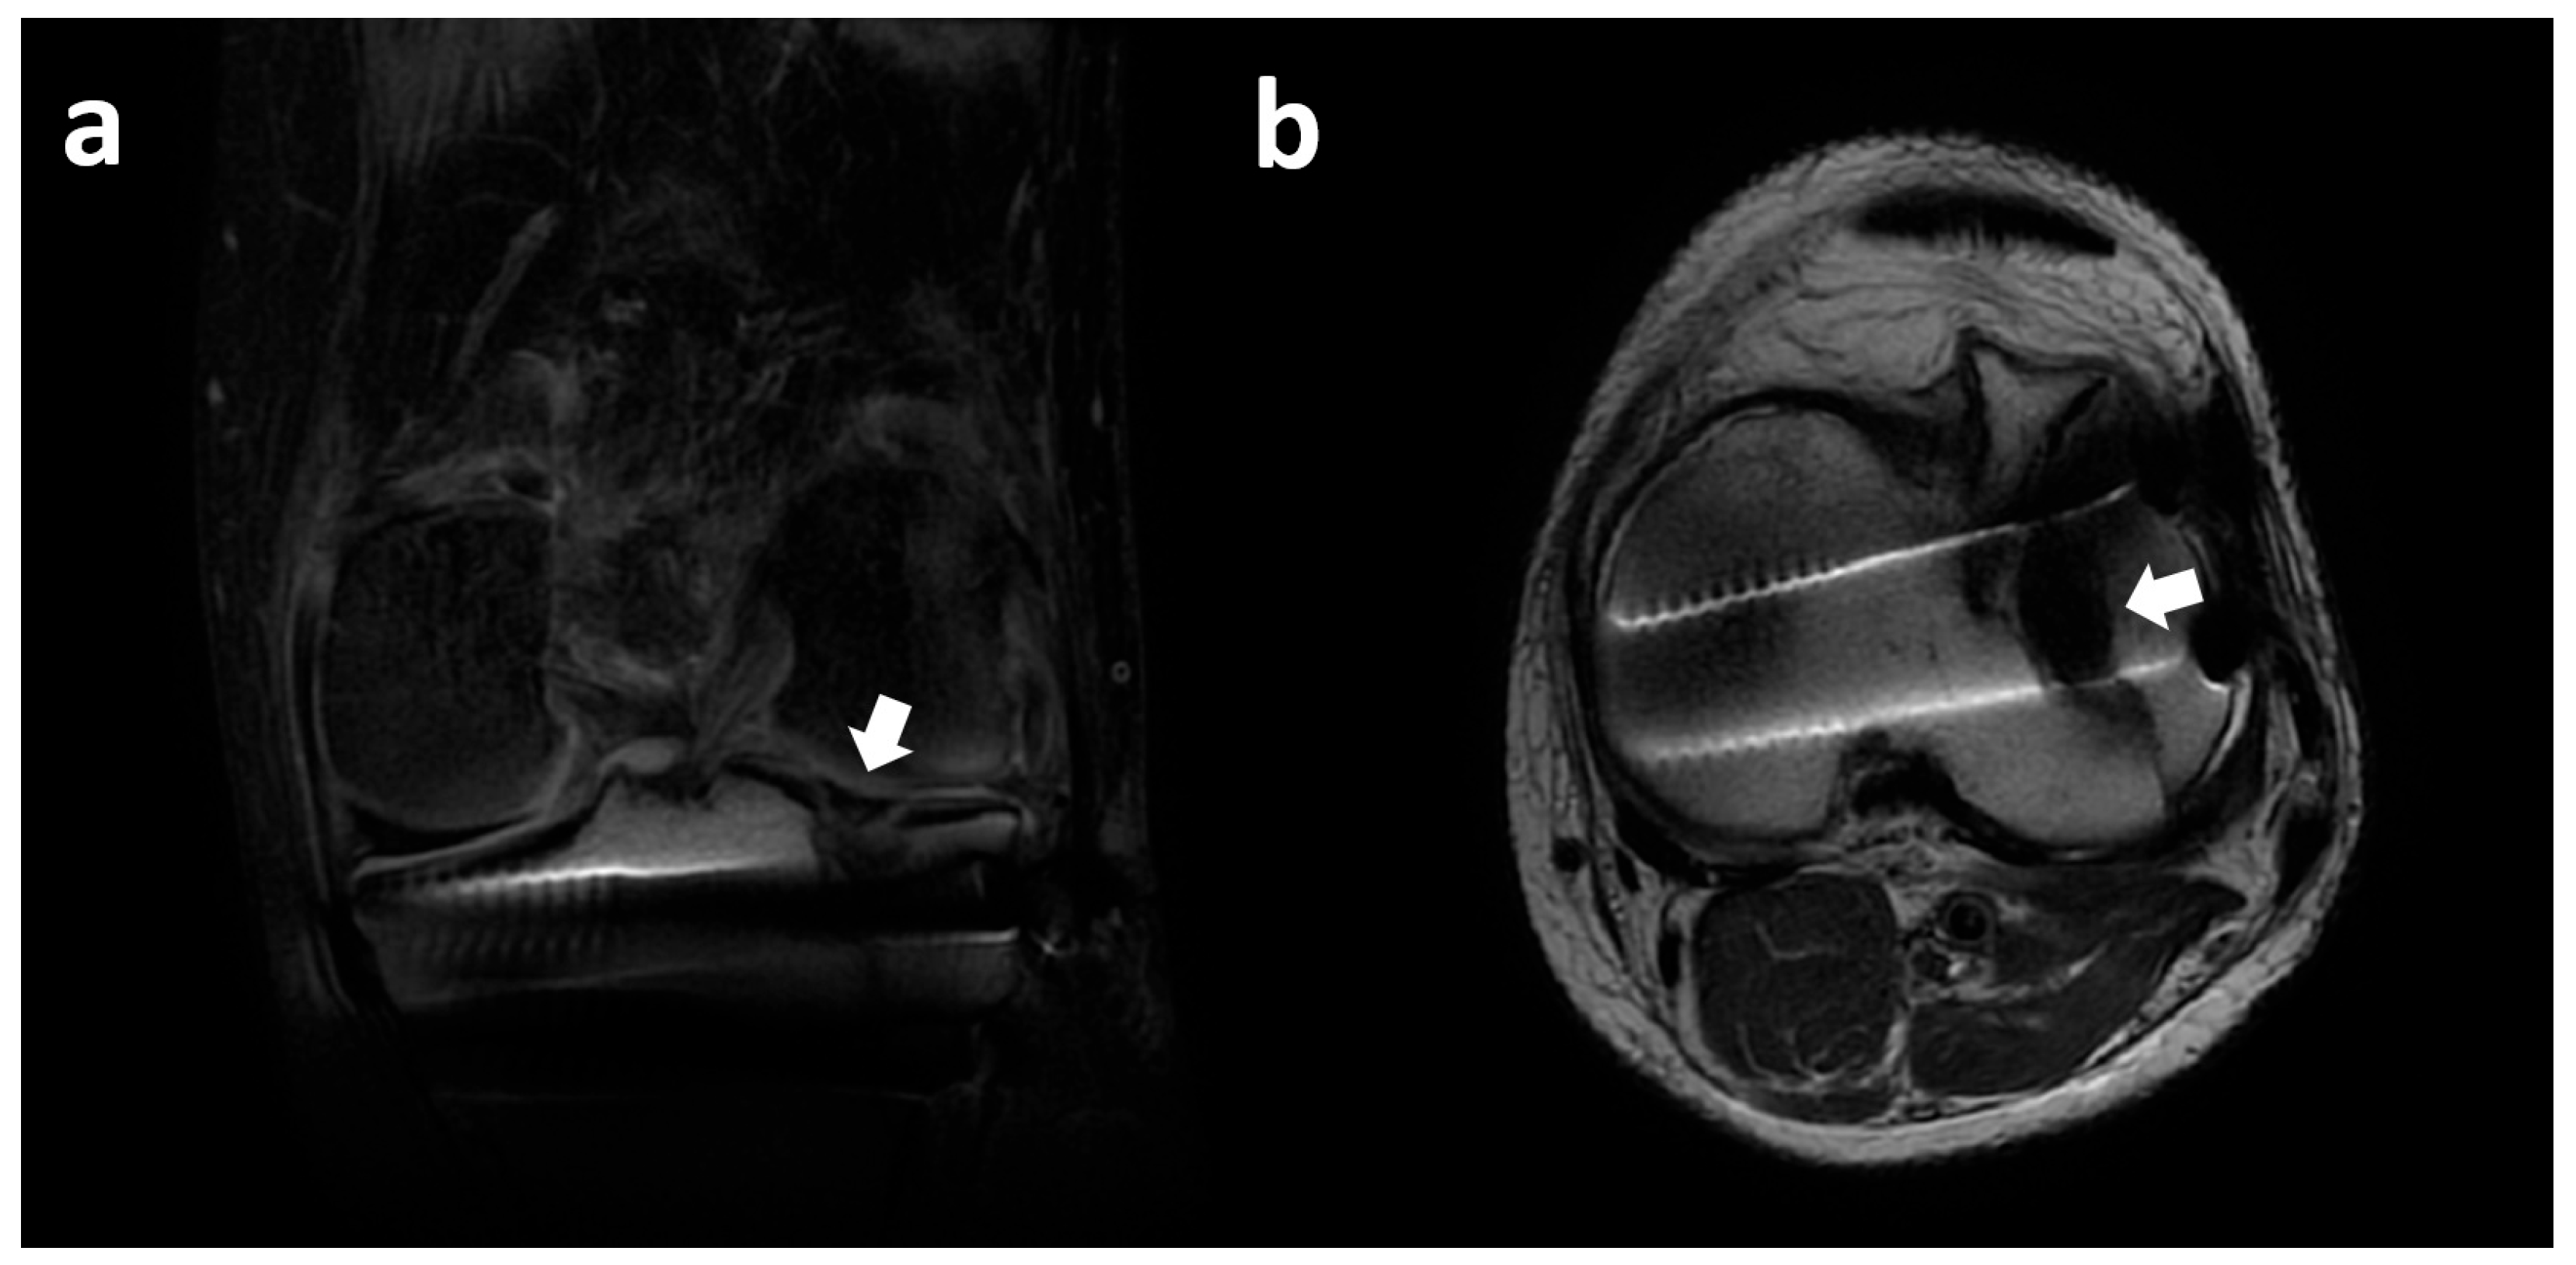

3.7. Lateral Meniscus Body Within Tibial Plateau Fracture